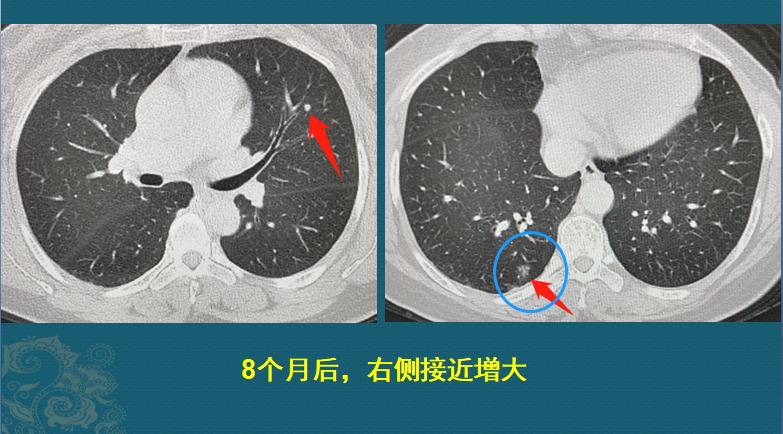

因为疫情缘故,她在8个月的时候回来复查了CT,左边的没有变化,右边的长大了:

8个月的时间,从一个不足3mm的微结节,长成9mm的磨玻璃结节,速度非常快!以至于我们不敢确定就是肺癌。